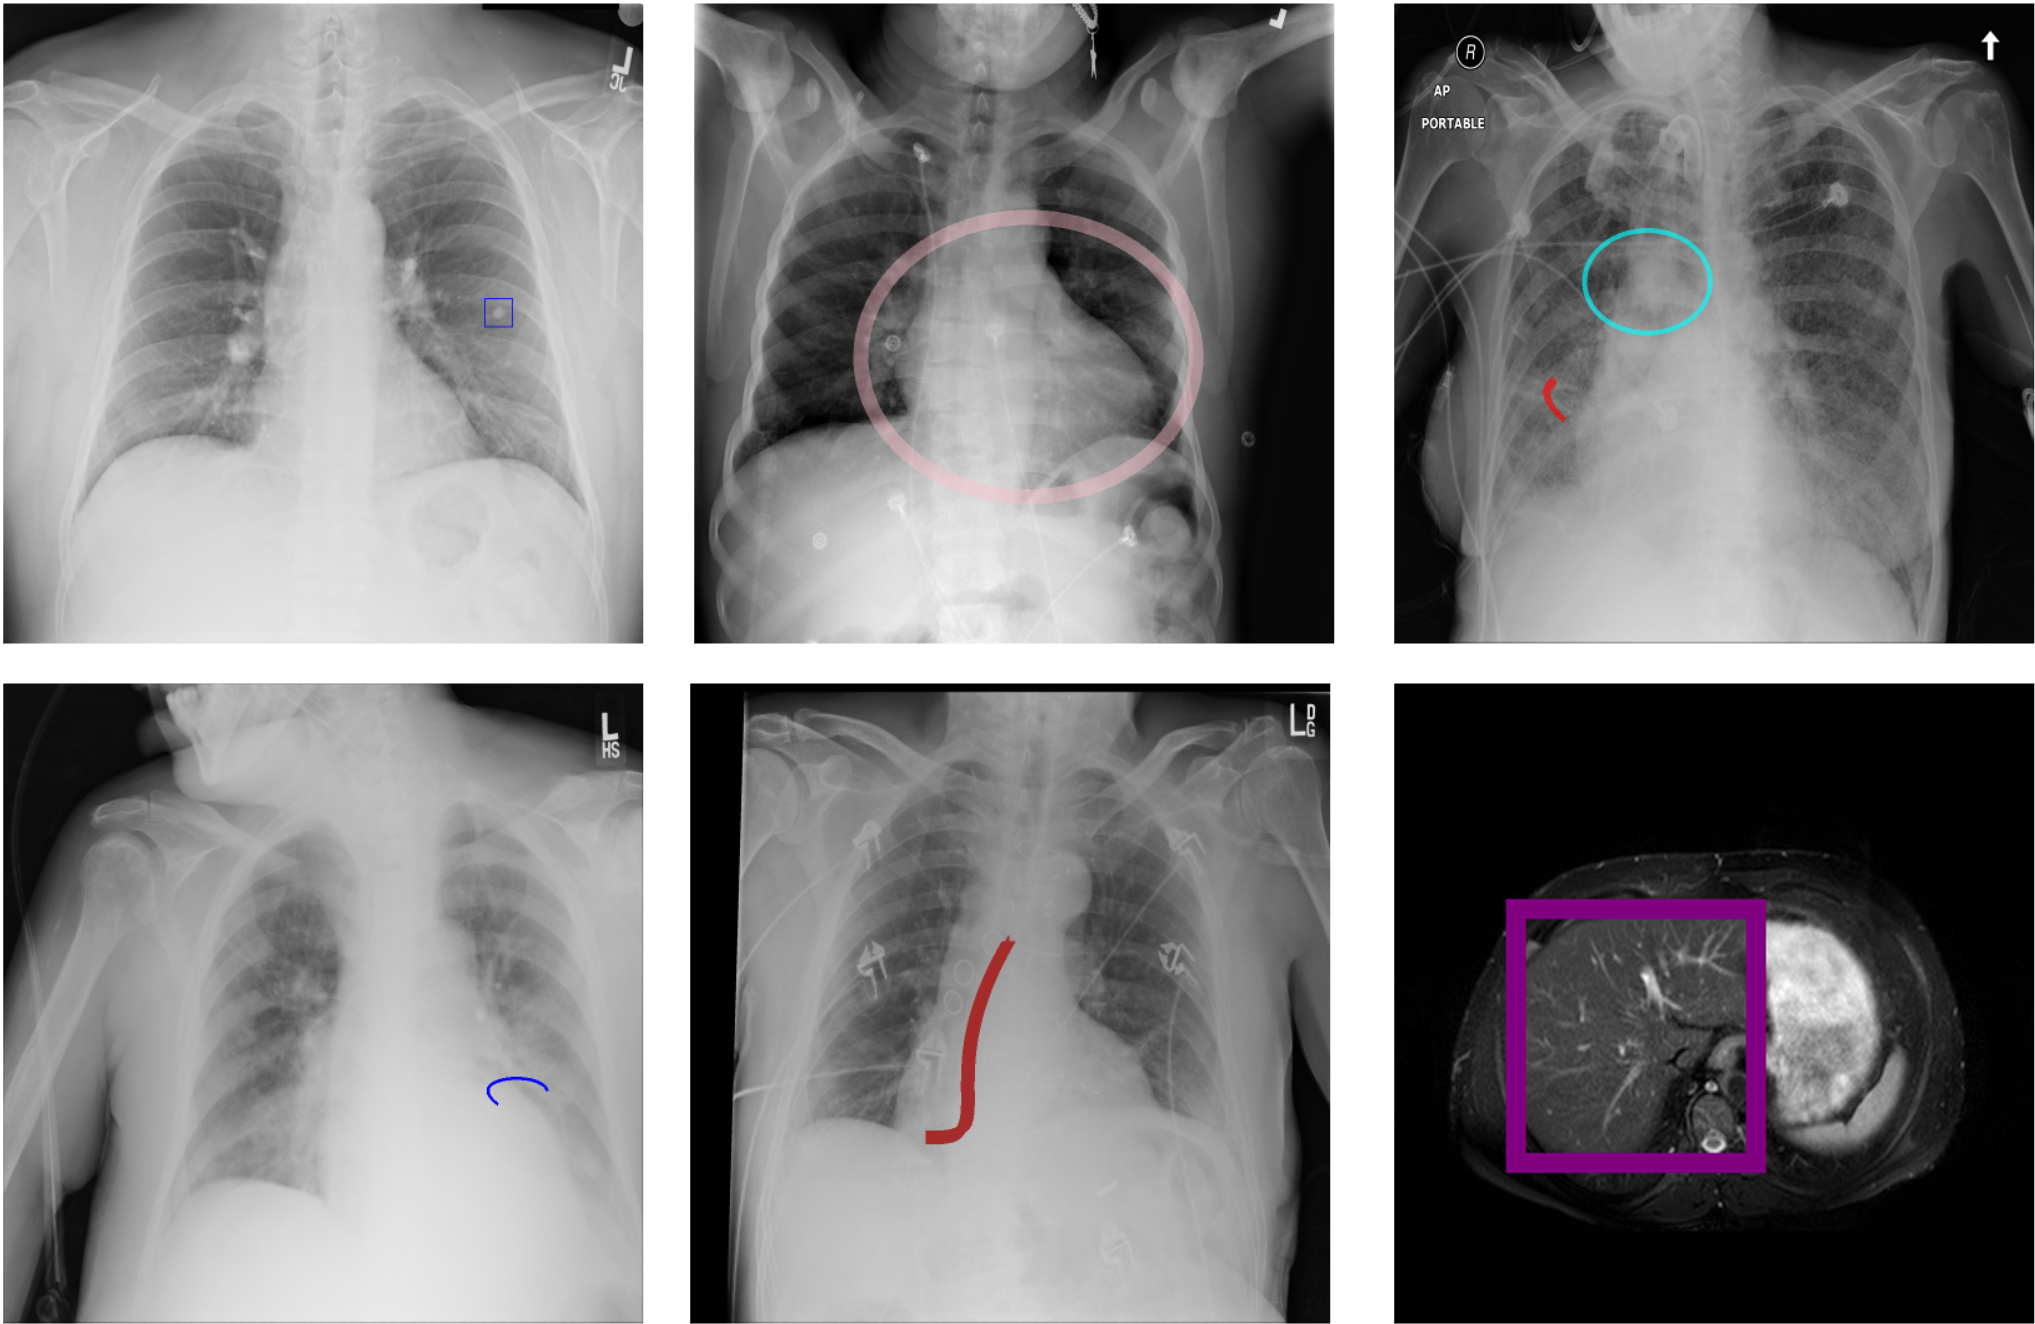

Appendix B Visualization of Visual Prompts

We present the visualization results of the integrated visual prompts in the images, demonstrating three types of visual prompts with varying sizes and levels of transparency.

Figure 6: Visualization of the visual prompts blended into medical images.